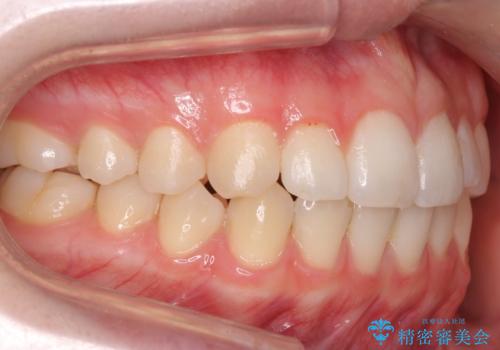

咬んでも前歯が閉じない 矯正治療で見た目を含めて改善

咬んでも向こう側が見える、前歯が閉じない症状でした。また、上の前歯が少し前に出ている状態でした。

上の前歯をわずかに削る処置を行い、後ろに下げながら下の歯となるべく咬むように矯正治療を行いました。